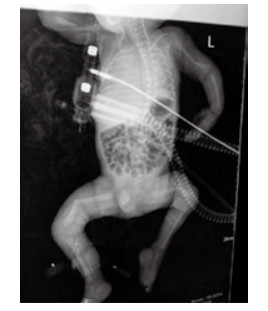

1 资料与方法孕妇20岁, 因“停经38周、阴道流液伴下腹坠胀1 h”于2015年9月10日23:45入住浙江大学明州医院产科。孕妇平素月经规律, 停经3个月在社区医院建卡定期产前检查, 停经17周产前筛查低风险, 停经20周自觉胎动无异常, 停经25周社区医院超声检查未见异常, 停经32周再次社区医院超声示胎儿臀先露, 羊水指数(AFI)22.5 cm, 余未见异常。既往体健, 无遗传病家族史, 孕期无病毒感染及放射线等不良接触史。入院查体:生命体征平稳, 发育正常, 营养可, 心肺听诊无异常; 腹膨隆, 宫高33 cm, 腹围99 cm, 胎位LSA, 胎心率140次/min, 先露臀、棘上3 cm, 宫口容1指, 羊水淡黄色。入院超声检查:宫内孕, 单活胎, 臀位, 双顶径9.3 cm, 股骨长7.4 cm, 头围33.4 cm, AFI 9.6 cm。因“臀先露”于9月11日02时09分剖宫产娩出一男活婴, 手术顺利, 重2 550 g, 身长50 cm, 面部外观未见异常, 四肢瘫软外翻、骨细小有骨擦感, 阴茎短小、睾丸未降, 1分钟Apgar评3分, 立即清理呼吸道、行气管插管气囊加压及呼吸机辅助呼吸等抢救, X线片示双侧股骨中下段明显成角, 左肱骨下段轻度成角, 右肱骨中下段不连续, 断端错位并轻度重叠移位(图 1)。新生儿抢救1 h后无效死亡。死亡原因:新生儿重度窒息, 新生儿骨软骨发育异常并多发性骨折, 死亡原因不明确申请尸检。

| 图 1 X线显示新生儿双侧股骨及左侧肱骨成交, 右侧肱骨骨折, 四肢骨及肋骨发育细小、骨密度减低 |

新生儿尸检报告:(1)成骨不全病(脆骨病); (2)双侧肱骨、双侧股骨病理性骨折; (3)双侧肘关节、腕关节、膝关节脱位, 桡、尺骨骨膜分离, 骨形态细小; (4)颅骨发育不全; (5)头皮帽状腱膜下出血; (6)心脏、大血管、双肺无畸形。